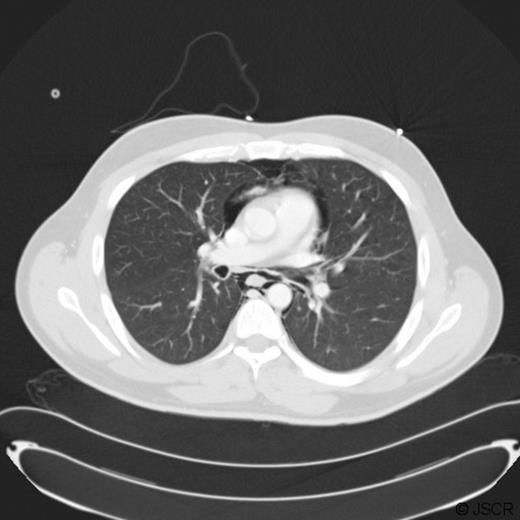

His blood tests showed a CRP 36, with all other hematological and biochemical parameters within normal levels. An electrocardiogram and serum troponin were unremarkable. A chest X-ray (Fig. 1) was performed to exclude pneumothorax but surprisingly revealed pneumomediastinum. He was admitted and transferred to the care of the surgical team with a diagnosis of suspected bronchial or oesophageal perforation. Computer Tomography (CT) Thorax imaging (Fig. 2) confirmed the presence of a pneumomediastinum extending from the lower neck at the level of C6 to the diaphragmatic hiatus. There were no visible mediastinal collections and no evidence of pulmonary /airway disease with intact pulmonary vessels. An oesophageal perforation was suspected but not shown on a water-soluble contrast swallow.